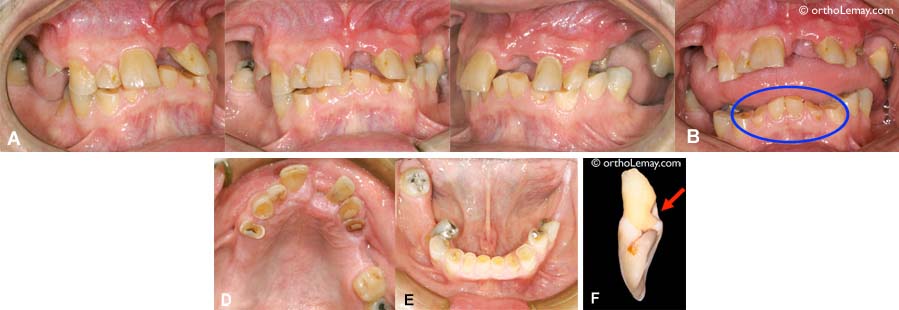

(A. B, C) Cette femme de 29 ans a un parodonte de qualité supérieure en général mais présente une incisive inférieure qui est complètement hors de l’arcade dentaire. Ce déplacement vers l’avant a causé une récession gingivale et une perte osseuse importante avant même que l’orthodontie soit débutée. Comparez cette dent aux autres dents qui ont un bon niveau de gencive. (D) Ce jeune patient (9 ans) présente une situation similaire.

Lorsqu’un parodonte est affaibli par la perte de tissus de support, des forces habituellement considérées comme “normales” peuvent devenir trop importantes pour être contenues par la dentition. Ainsi, dans le cas de ce jeune adulte de 24 ans, le parodonte des dents antérieures présente une perte osseuse importante. La langue, déjà “hyperactive” dans cette bouche, constitue maintenant une force trop importante pour que les dents puissent lui résister. Il s’ensuit donc des déplacements dentaires; les dents antérieures basculent vers l’avant et s’espacent. (A) Position de “repos” habituelle; la langue exerce une pression constante contre les dents. (B) Façon de mordre lorsqu’on lui demande de reculer volontairement sa langue et de “forcer” pour fermer ses dents ensemble. Note : La couleur foncée de la gencive est due au fait que cette personne est de race noire. Les résultats du traitement d’orthodontie et de parodontie sont illustrés ci-dessous.

(A) Cet homme dans la cinquantaine est un bruxeur chronique. Il est aussi affecté par des problèmes parodontaux qui ont causé une perte osseuse importante au cours des années. Ceci, couplé aux forces excessives générées par le bruxisme, a eu des effets dommageables pour cette dentition et cette occlusion. L’incisive supérieure gauche était tellement mobile qu’elle est tombée (voir F). Cette dent avait un trou causé par la dent inférieure qui la frappait toujours au même endroit (flèche). (B) Les incisives inférieures sont usées à 50-70%. (D, E) Aucune dent n’est épargnée par cette usure excessive, sauf les dents qui ne touchent pas à une dent opposée.